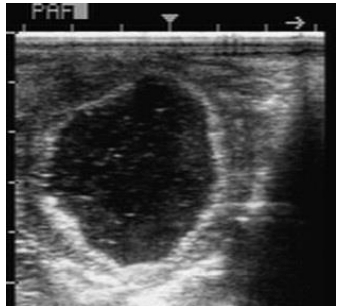

What is this in the ovary and what is it caused by? (2)

AHF (anovulatory haemorrhagic follicle)

Anechoic, irregular wall, ‘snowball’ fibrin speck effect

Idiopathic lack of LH surge → failure to progress ovulation

(some suggest PGF2a treatment but most eventually regress with time to return to normal cycling)